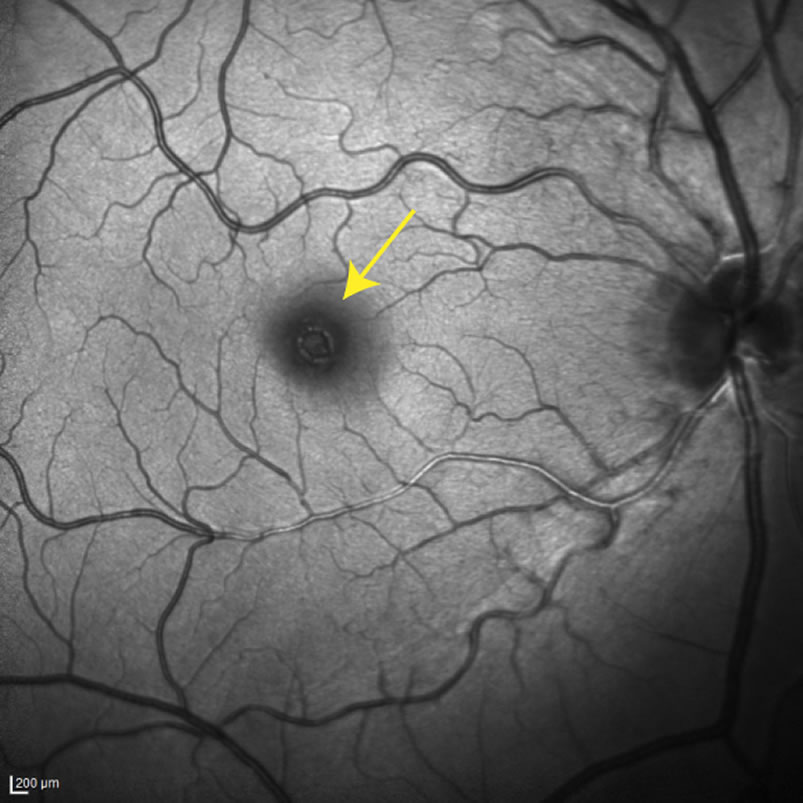

macula hole

Macular hole is caused by abnormal aging of the vitreous gel. The very center of the macula is very thin and delicate. The aging vitreous gel somehow pulls in a wrong direction and causes a tiny rip in the macular center. Over the subsequent weeks, the tiny rip gets bigger and a full-thickness macular hole develops.

There are other causes for macular hole, such as a severe eye injury, or near-sightedness. But most commonly, macular hole is due to abnormal aging of the vitreous gel.